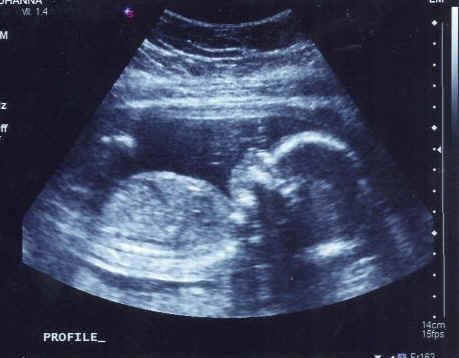

3.试管婴儿B超监测法。试管婴儿医院通过B超来监测排卵的方法较为准确,试管婴儿B超观察卵泡逐渐增大,在试管婴儿排卵日的前3天可达到19mm,试管婴儿准妈妈排卵当天会增大至20mm以上。观察日如果正好是试管婴儿排卵日,有时甚至可以在超声波上看到试管婴儿卵泡破裂。但是试管婴儿周期需要连续监测3-5次。